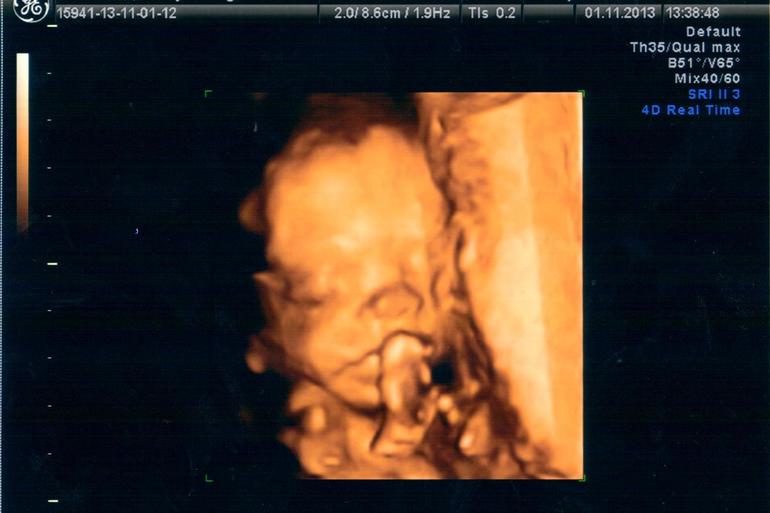

Сегодня я по особенному счастливая и наш с пузиком экватор - не единственная тому причина, причин у нас много - сегодня мы были на УЗИ (подглядывали за нашим сокровищем), до сих пор эмоции переполняют… :) У нас все хорошо, развиваемся по сроку, уже довольно-таки большие - 330 грамм )) Мы узнали пол, я аж прослезилась от счастья ))) Муж тоже очень рад, от чего я счастливее вдвойне )))

Собственно говоря, вот и мы:

На УЗИ мы спали, так что выкрутасов типа сальто мы не увидели (как на 12 неделях), но УЗИстка сказала запасаться книгами по воспитанию, т.к. ребеночек уже очень характерный )) А еще очень скромный, малыш закрывал себе постоянно личико, при чем не всегда ручками, бывало и ножками )) От этого мне пришлось постоянно вертеться с бока на бок и кашлять, чтобы хоть как то заставить его показаться нам, в конце даже удалось разбудить. Нам сделали аж 12 фото и 24 видеоролика )))